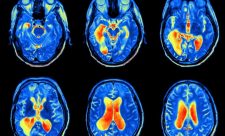

מהי מגנטיזציה אורכית? MRI - מושגי יסוד ופיזיקה

מגנטיזציה אורכית (longitudinal magnetization) היא מרכיב של וקטור המגנטיזציה הכולל בכיוון השדה המגנטי הקבוע. פולס הרדיו גורם להפחתה של מרכיב זה עד כדי ביטולו, ולאחריו הוא חוזר בהדרגתיות למצבו הראשוני. זוהי בעצם המגנטיזציה של גוף האדם אשר אותה אפשר להטות למגנטיזציה רוחבית ואז להצליח למדוד אותה. את שיקום המגנטיזציה האורכית, לשם הבדלה בין הרקמות